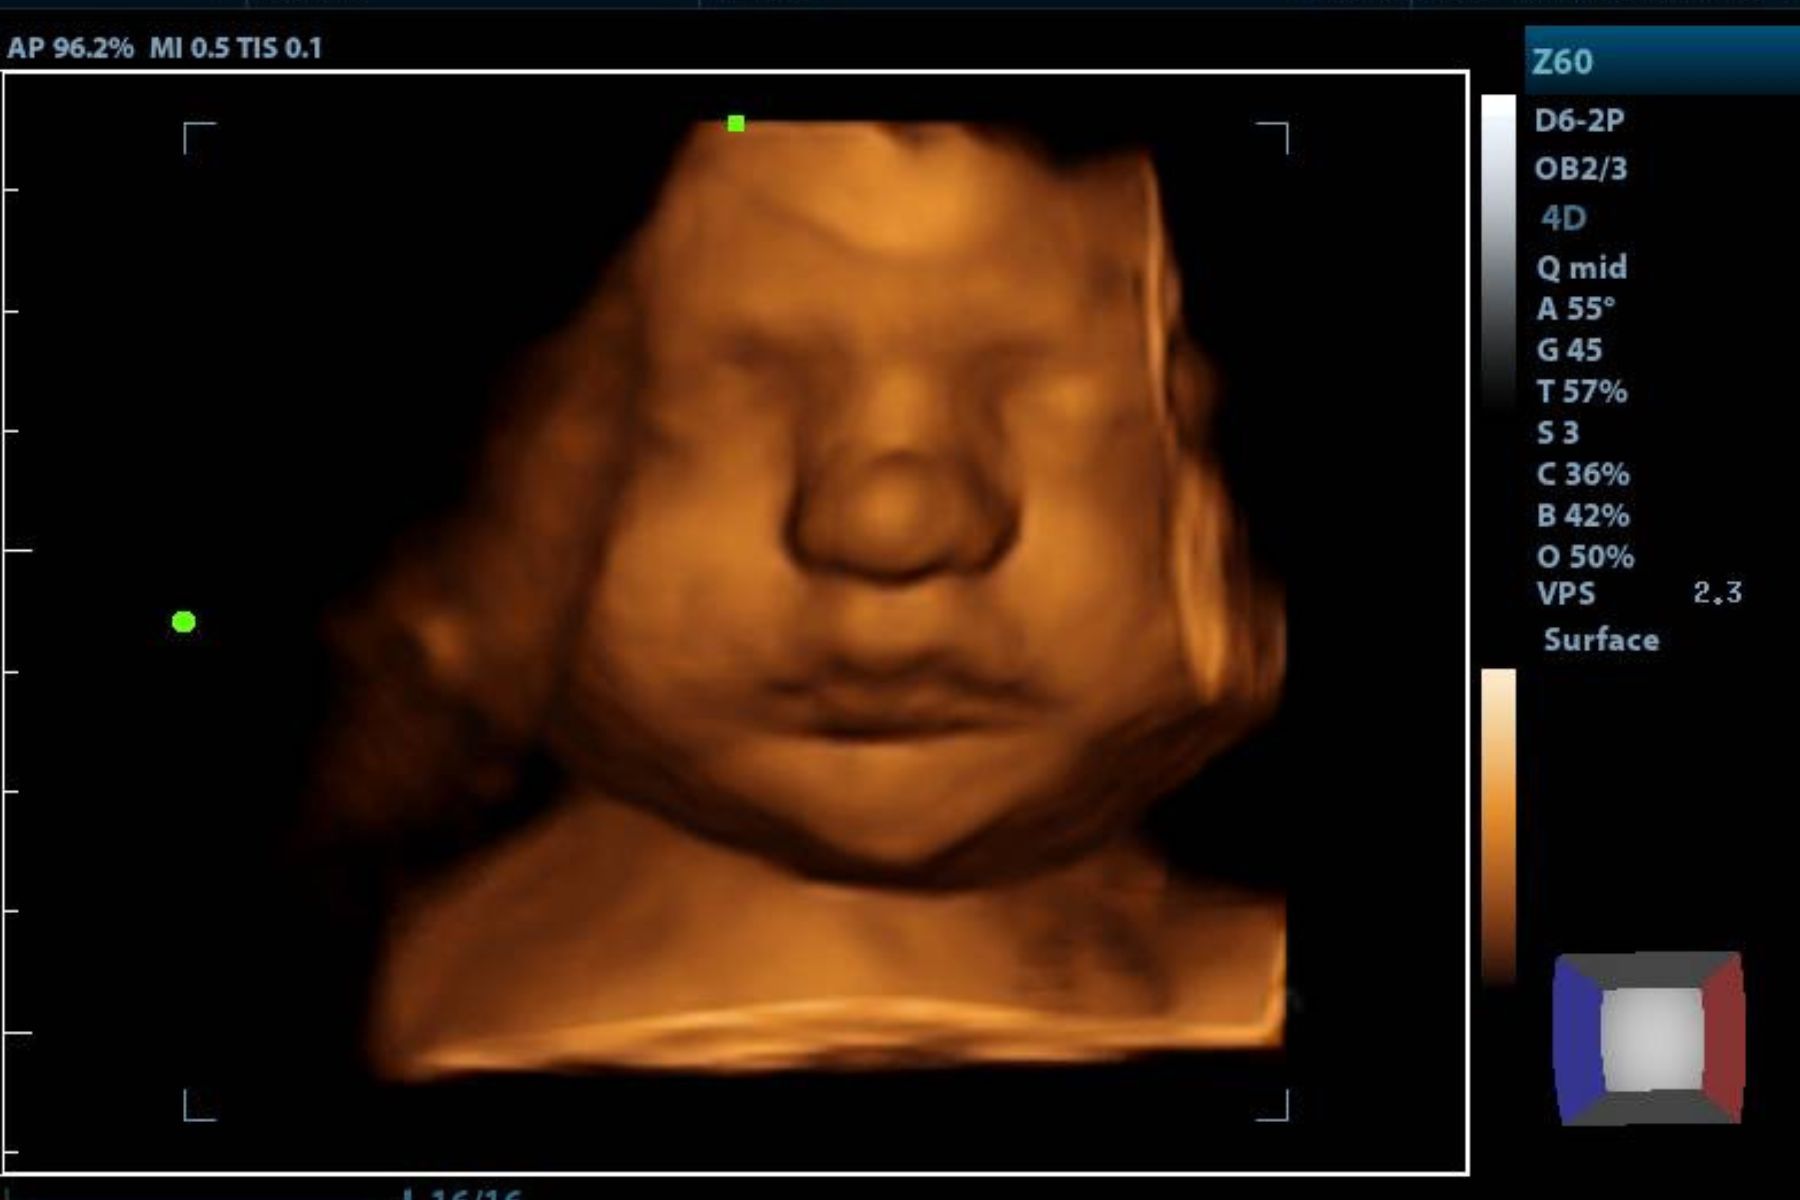

2d, 3d,4d & HD live

At your appointment, we connect directly to your home TV via HDMI, so everyone can enjoy a crystal-clear view. You’ll receive printed keepsake photos in the mail, plus digital images and video recordings delivered straight to your email.

Enjoy a private, affordable ultrasound from the comfort of your home, perfect for moms between 7–41 weeks. Share the moment with loved ones by connecting directly to your TV for real-time viewing in 2D, 3D, or 4D. Ideal for baby showers or gender reveal parties!